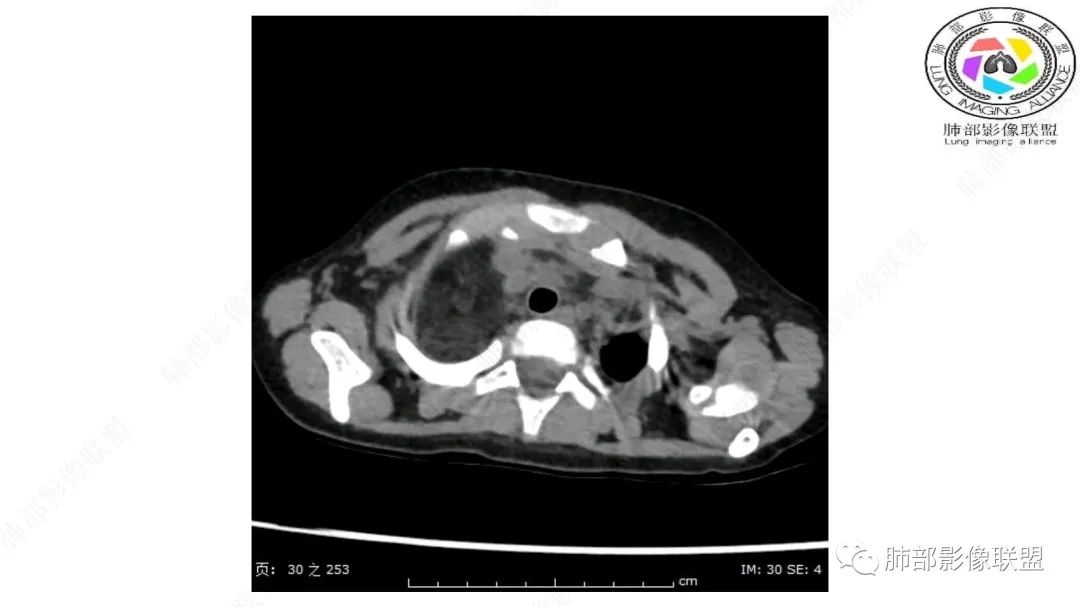

右上纵隔混杂密度肿块,边缘光整,与纵隔分界清,其内多发脂肪密度,增强无明显强化,其内血管穿行,考虑纵隔脂肪母细胞瘤,鉴别畸胎瘤,脂肪肉瘤。

3岁儿童,右纵隔占位,内部间多发脂质成分及斑片状稍高密度影,考虑纤维成分,增强似有强化。病灶内血管未见明显侵犯,可考虑脂肪母细胞瘤,冬眠瘤等。

三岁小儿,右侧纵隔巨大脂肪密度肿块,肺动脉穿行其中,密度欠均匀,未见明确实性成分,纵隔脂肪母细胞瘤,冬眠瘤鉴别纵隔脂肪增多症(多弥漫对称)。

患儿3岁 咳嗽检查发现纵隔占位。右肺上叶受压表现,占位以脂肪组织密度为主,似见分隔,首先考虑为脂肪母细胞瘤,鉴别脂肪瘤,畸胎瘤。

幼儿,右上纵膈团块,脂肪密度,内见分隔,增强病灶内见血管穿行,结合患者年龄,考虑脂肪母细胞瘤,鉴别脂肪瘤。

纵隔畸胎瘤,右前上纵隔团状脂肪密度?粘液样密度为主病变,病灶软边缘有分叶,内可见分隔,增强后血管穿行。3岁。考虑纵隔脂肪母细胞瘤,鉴别畸胎瘤。

病灶属于交界区,主体位于肺内,占位效应明显,前方突入胸壁,胸腺受压变形,胸膜显示欠清楚;病灶包绕上叶肺动脉;似乎有体动脉供血。符合肺内的点:包绕上叶肺动脉分支;符合纵隔的点:前方似乎突入胸壁,与胸腺关系比较密切,但是与上腔静脉的关系提示病灶不支持纵隔来源,前纵隔的常规会将上腔静脉受压后移、外移,这是不符合的。

手术记录:见右肺上叶肿物,肿物与右肺上叶关系密切。与纵隔无粘连,逐步分离肿物,见肿物大小约6cm*5cm,边界清楚,于右肺上叶粘连,边界清楚,肿物包绕右肺上叶血管及支气管。超声刀逐步游离肿物,完整切除肿物,右肺上叶肺组织无破溃,表面无出血。

2.肺动脉穿行也许是肺内来源最重要支持点!

脂肪母细胞瘤由成熟程度不同的脂肪组织、纤维间隔、黏液基质、小血管丛等间质成分组成,以脂肪组织与黏液样基质为主,其影像学表现取决于上述组织成分。典型的CT和MRI表现为:前后纵隔均可发生,常见于前纵隔;肿块大小不一,直径多在3cm~7cm,密度均匀,CT值呈水样或脂肪密度,脂肪组织密度或信号为主的肿块,其内密度或信号不均匀,可见粗细不一的分隔影,且有结节、片状影,后者可呈轻中度强化;结节状肿瘤包膜完整;弥漫性者包膜不明显,常呈浸润性生长;周围结构为受压和推移改变,可有少量胸腔积液,淋巴结无增大。